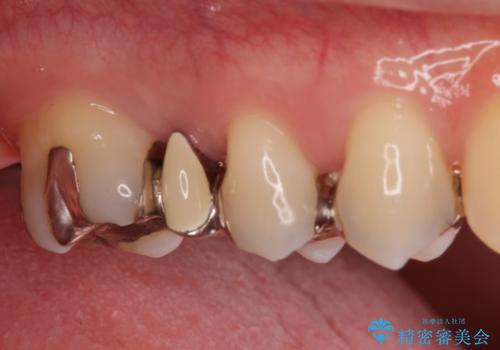

- 銀の詰め物、被せ物を白くしたいとのことで来院。

銀のところはインレーブリッジになっており、外してブリッジを入れたいが奥の歯が前に倒れ込んでおり、

ダミーの歯の部分(ポンティック)のスペースが狭いため無理やり作るとインレーブリッジと同じように小さい歯が出来てきます。